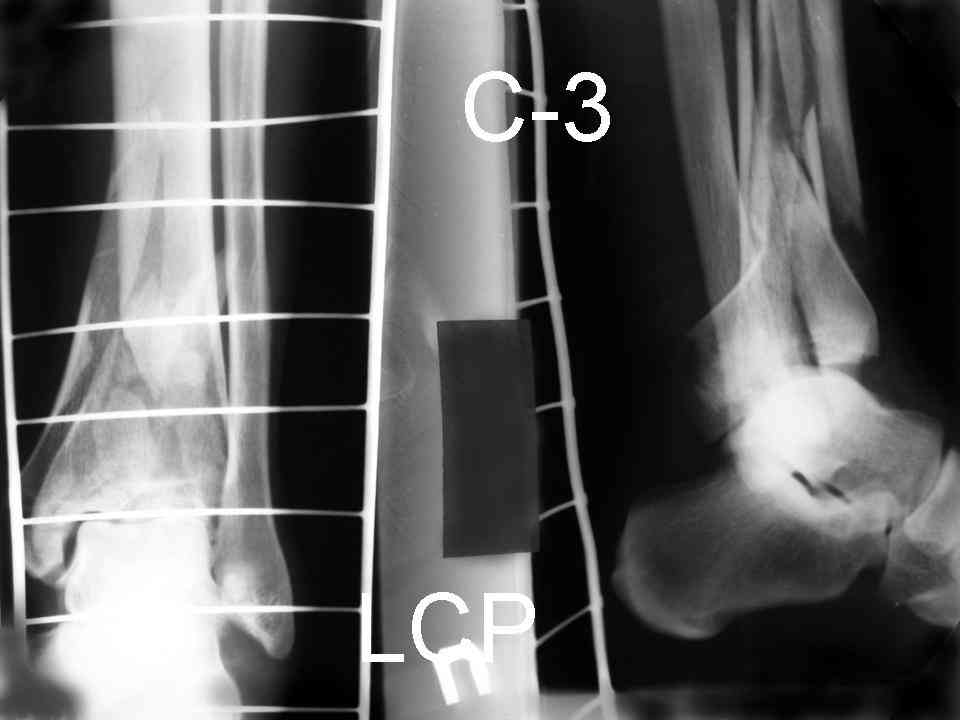

На рентгенограммах типичный перелом пилона по типу С-3. есть опыт до 100 открытых опреаций у нас в клинике. 20 примерно в год. Принцип один -все внутрисуставные переломы нуждаются в открытой репозиции и внутренней стабильной фиксации. При поступлении КТ не надо, так как получается только нагромождение костей. Истинной картины нет. Главное восстановить длину малоберцовой кости - это ключ к успеху. При поступлении меньше всего надо думать о сосудистых расстройствах, т.к. сама операция и репозиция даже сначала частичная даёт улучшение сосудитых нарушений. Причём очень быстро. Операция в 2этапа. При поступлении доступ позади наружной лодыжки, причём обязательно. После этого репозиция малоберцовой кости и фиксация пластиной 1/3 трубки под винт 3,5. Дренаж и любой аппарат наружной фиксации. Затем после спадения отёка на 5-7-10 день аппрат снимается и дугообразный разрез спереди от медиальной лодыжки 10-12 см. Главной чтобы расстояние между 1 и вторым разрезом было не меньше 7-8 см. Тогда не будет некрозов лоскутов. Таранная кость используется как матрица на неё укладываются отломки и фиксируются пицами. Ренг-контроль. Отломки лежат все отдельно, но ничего не высыпется. При переломах С-3 всегда нужна костная пластика (из крыла). Фиксация пластиной лист клевера простой или LCP. Гипс не нужен. Дренаж до 48 часов. Операция длится 3-4 часа обязательно без жгута. Посылаю примерно такой же случай.

Послала ещё два снимка, если не пройдут, пошлю ещё. Дрягин. Если есть вопросы, готов ответить.

Посылаю результат лечения предыдущего больного через год.